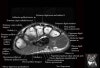

- Coronal section

Coronal T1 imaging evaluates bone marrow signal (ex. increased in avascular necrosis) and the relationship of the osseous structures to each other (ex. scapholunate disassociation).